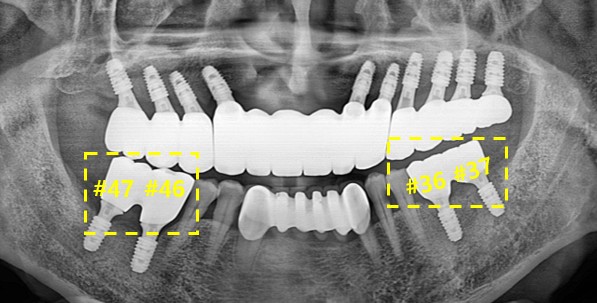

하악의 치아는 #47 46 # 37 36 임플란트 식립 전치부의 치아는 살려 두는 방향으로 치료를 진행 하였습니다.

환자분도 치료에 적극적으로 해주셔서 최종 치료 소요 기간까지 7개월 정도 되었습니다 .

심리적으로 자신감도 찾으시고 기본적인 생활의 질적으로도 매우 만족하셔서 감사드립니다.

이제는 제가 눈으로 보기에도 기분이 좋고 식사할때도 편해서 너무 만족 합니다.